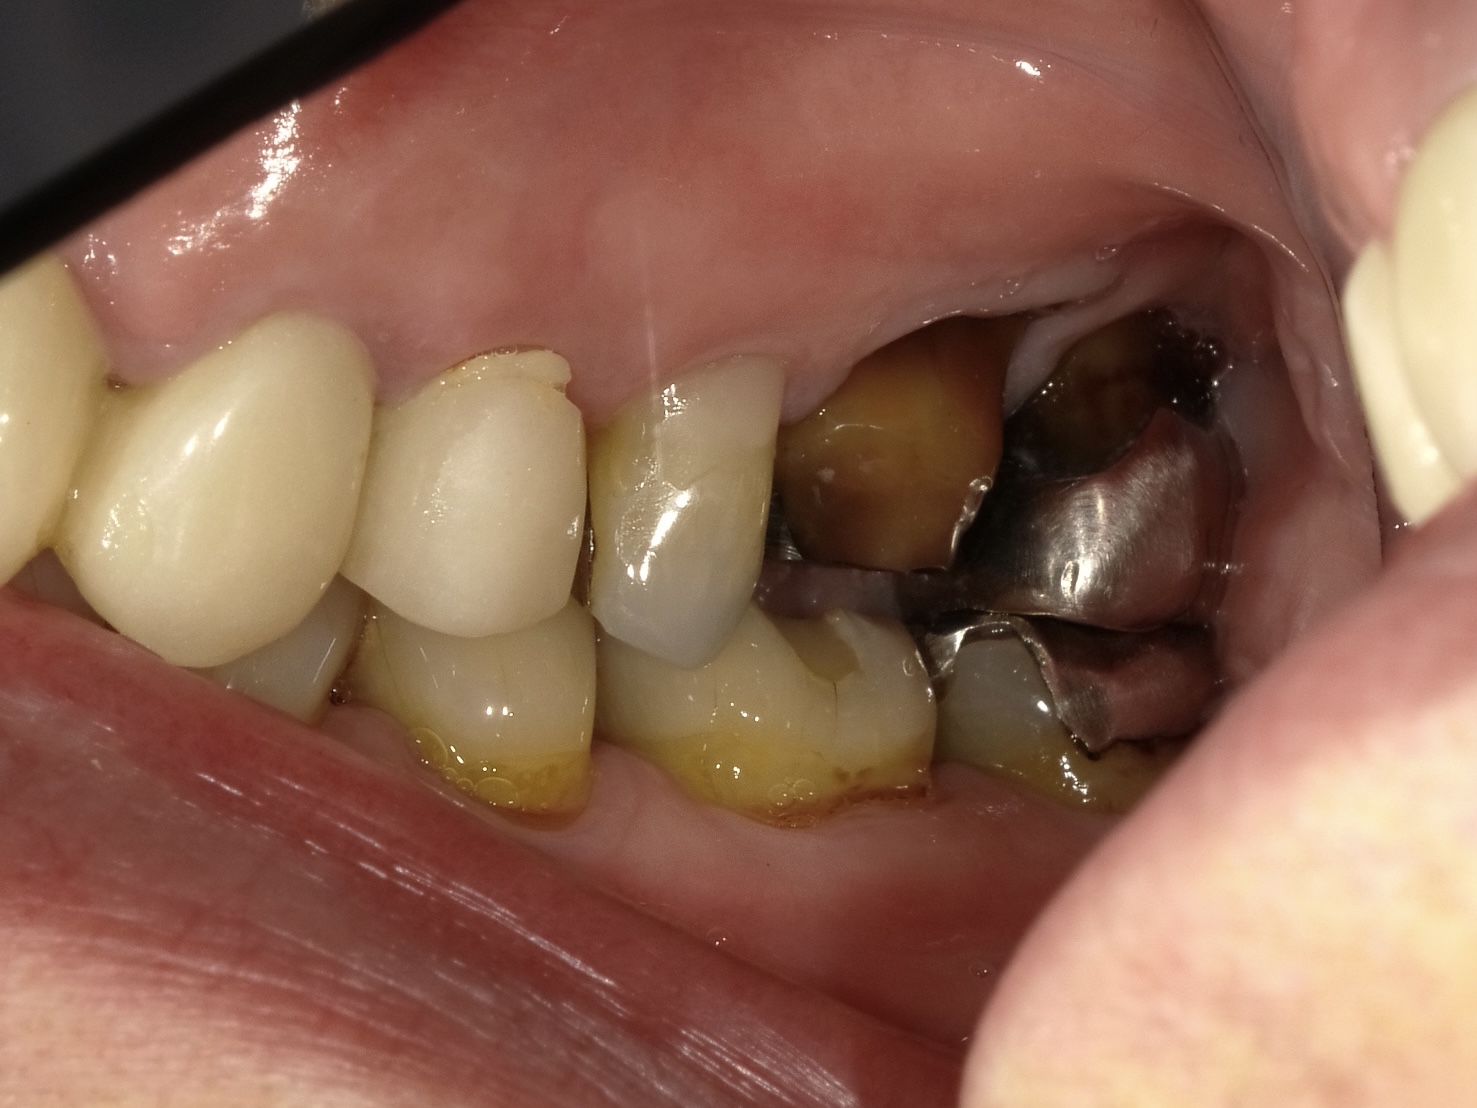

左上6番 抜歯即時インプラント埋入

BEFORE

AFTER

| 金額 | ¥450,000(税抜) |

| 期間 | 約3ヶ月 |

| リスク | オペから6週までは過大な力がかかると骨の2次安定が得られないことがあるため、注意を要する。 |